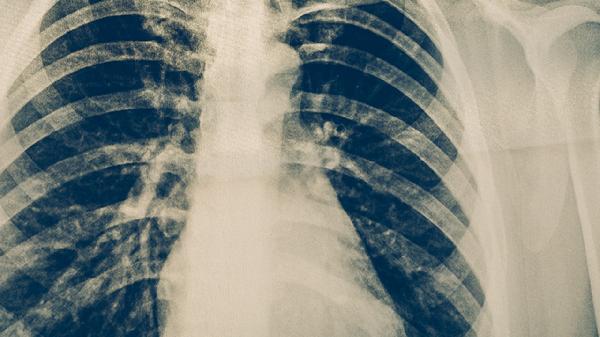

肺结核复发通常不好,可能提示治疗不彻底或再次感染,需及时就医调整方案。肺结核复发可能与耐药性结核分枝杆菌感染、不规范用药、免疫力下降等因素有关,常表现为咳嗽加重、低热、盗汗等症状。

肺结核复发时,病原体可能对既往药物产生耐药性,需通过痰培养和药敏试验重新制定方案。常见治疗药物包括异烟肼片、利福平胶囊、吡嗪酰胺片等,但需根据检测结果选择敏感药物。若未及时干预,可能引发肺空洞、咯血甚至播散至其他器官。

复发期间需严格隔离,避免传染他人。患者应保持充足睡眠,每日摄入高蛋白食物如鸡蛋、鱼肉,并补充维生素C丰富的柑橘类水果。居住环境要通风良好,佩戴口罩遮挡飞沫。康复期间定期复查胸部CT和痰涂片,直至医生确认病原体清除。